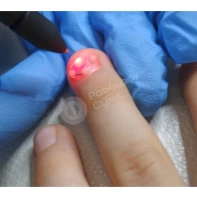

При хирургическом лечении хирург обрабатывает рану под местным обезболиванием. Далее аккуратно резецируется край ногтевой пластинки с учетом ее будущего роста. Затем специальным электродом выполняется коагуляция участка матрицы, из которого росла резецированная часть ногтевой пластинки. Последний этап операции – наложение повязки с антибактериальной мазью. Швы не накладываются, эстетика пальца не изменяется.